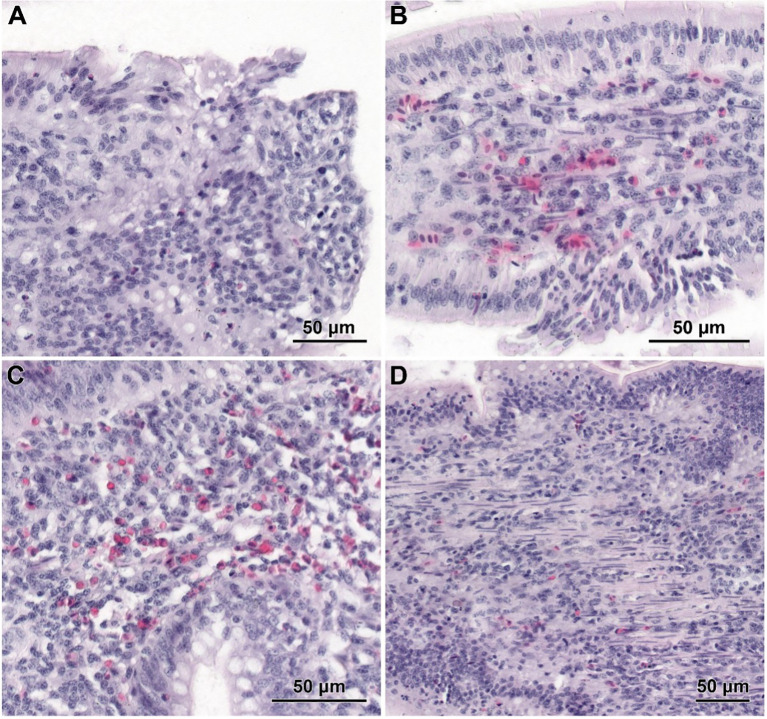

The electron microscopy study of the jejunum

In non-infected chickens (groups C and CBD + nano-Se), the epithelium of the villi consisted of a continuous and regular layer of columnar cells connected via tight and anchoring junctions located near their apical poles (f5). Microvilli covering enterocytes were regularly distributed but not very densely packed. The layer of cortical actin filaments was well-developed. The apical parts of enterocytes comprise mitochondria with a matrix of moderate electron density, Golgi apparatus and both forms of the endoplasmic reticulum. Lipid droplets were sparse in these cells. The goblet cells contained large secretory granules. Lymphocytes were sparse to moderate in number. The intestinal glands comprise immature enterocytes and goblet cells, as well as enteroendocrine cells (f5). Injured cells were extremely rarely found.

Electron microscopy revealed the presence of small necrotic regions within the epithelium covering both the apical and lateral surfaces of the intestinal villi in chickens infected with C. perfringens (f6). In addition to necrotic cells and cellular debris, these regions comprised abnormal enterocytes lacking cell polarity and microvilli. The cell debris was also present in the intestine lumen over the necrotic regions. The apical portions of villi, described at light microscopy level as devoid of the epithelium cover, contained necrotic cells, cellular debris, and numerous inflammatory cells, but also irregularly shaped enterocytes without microvilli (f6). Enterocytes in these areas were loosely attached and did not form the tight junctions. Ultrastructural analysis also revealed areas where enterocytes formed a continuous or nearly continuous layer but were highly irregular in shape and devoid of microvilli (f6). The stroma of some villi contained numerous inflammatory cells, frequently with foamy cytoplasm (f6) and an increased presence of smooth muscle cells (f6).

Infected chickens treated with CBD, CBD + nano-Se, or nano-Se displayed similar ultrastructural changes as those infected with C. perfringens but not supplemented with these compounds (f7). Necrotic foci covered with cellular debris (f7), areas of abnormal epithelium containing irregularly shaped enterocytes without microvilli (f7), intense infiltration of the epithelium by lymphocytes (f7), and the presence of inflammatory cells with foamy cytoplasm in the villi stroma (f7) were common across all infected groups receiving CBD, nano-Se, or CBD + nano-Se.

Light and electron microscopy analyses were performed to assess the histological structure and ultrastructure of the intestine. These studies showed that CBD + nano-Se supplementation is safe for the gut and does not cause negative qualitative changes in the histological structure of the small intestine and the ultrastructure of the jejunum. This result is partly consistent with a study by Gangadoo et al. (ref. 54), who showed in a histopathological analysis that nano-selenium did not cause harmful effects, revealing intact epithelial cells in the gastrointestinal tract in broiler chickens. This result also confirms the current authors’ previous study (ref. 32), which found that the combination of these two nutritional additives showed no opposite effect on mediating the host response to infection. This confirms that understanding the mechanisms of action of cannabidiol and nano-selenium is of great interest in developing new possibilities for promoting intestinal barrier function. In the present experiment, C. perfringens infection did not cause necrotic enteritis. The changes were moderate in character and mainly involved damage to the intestinal epithelium. This correlates with the clinical condition of the chickens, as none of the challenge tests induced overt clinical signs of NE. According to Timbermont et al. (ref. 16), NE is characterized by a strong inflammatory response in its early stages, where the most significant early changes are seen at the interface between the enterocyte domain and the lamina propria. An ultrastructural study by Olkowski et al. (ref. 55) shows that primary modifications occur at the level of basal and lateral domains of the enterocytes. In contrast, the apical domain of enterocytes remains intact even in the face of advanced necrotic changes. This indicates that mucosal necrosis does not result from direct damage to the mucosal epithelium. Rather, the necrotic death of enterocytes is a consequential effect of destroying lamina propria, the extra-cellular matrix, and intercellular junctions. This result is consistent with the study of Olkowski et al. (ref. 56), who also found no overt mucosal necrosis typical of NE field cases in a histological examination in C. perfringens-infected chickens. This is very important because the current study aimed to induce a moderate infection, mimicking a subclinical infection rather than the acute form. It should be mentioned here that increased collagenolytic enzyme activity in the mucosal and intestinal tissue environment is an integral component of the pathological process leading to NE (ref. 32, ref. 55). However, none of the supplements administered had a remarkable effect on the morphological changes in the gut developed during infection. Perhaps it was too short a time to see changes at the microscopic level because, at the molecular level, treatment with nano-Se and CBD significantly increased the mRNA expression of genes such as junctional adhesion molecule 2 and zonula occludens-1, which are responsible for intestinal integrity (ref. 32, ref. 33). In addition, in a previous study, the authors also showed that cannabidiol and nano-selenium in C. perfringens-infected chickens promoted changes in the extracellular activity of bacterial enzymes in the gut, which may indicate increased energy consumption under induced stress conditions (ref. 32).